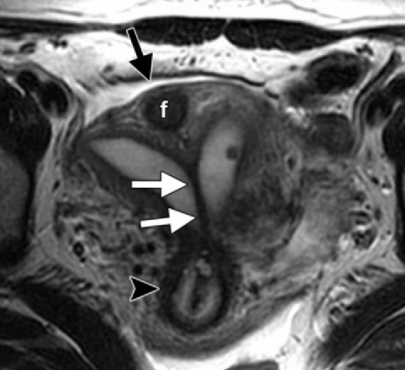

Utérus Bicorne

Bicorne VS Septé